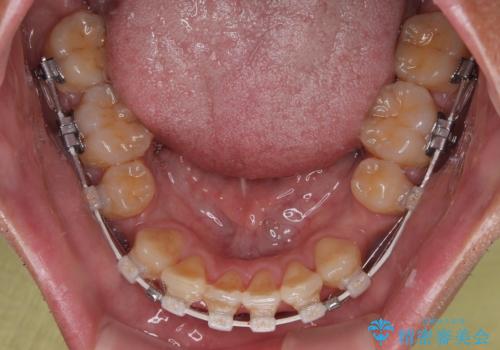

使用した装置は、透明感のあるプラスチックブラケットと白くコーティングされたワイヤー。

金属の装置に比べて目立ちにくく、治療中も自然な見た目を保ちながら矯正を行うことができました。

舌を前に押し出す癖(舌突出癖)があり、後戻りやオープンバイトの再発防止のため、MFT(口腔筋機能療法)も併用しています。